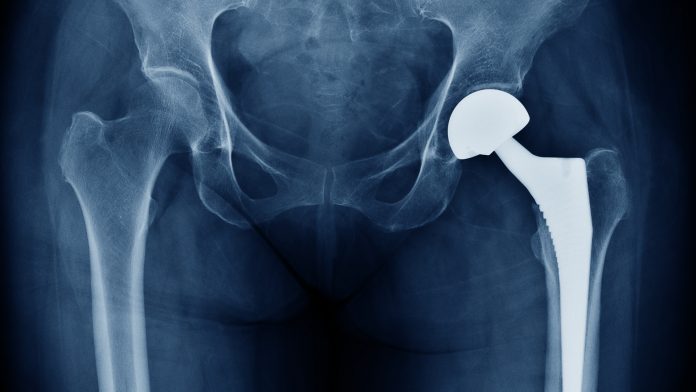

Researchers from Tomsk State University, Russia, have patented a method to create a material for bone implants that reacts to weight in the same way as living human tissues.

The team used a porous powder alloy, based on titanium nickelide with titanium powder additives, to create the material. The additives made it possible to regulate the porosity, whilst also allowing the material to behave like elastic and offer significant shape memory. The properties of the new material are comparable to how the bone tissues of the human body behave under physiological stress.

Due to the implementation of phase martensitic transformations, the alloy based on titanium nickelide possesses the same hysteresis pattern under stress. That is why implants made of this material meet the latest medical requirements in surgery, dentistry, and traumatology.

The elastic porous material can change its shape by up to 6–7% without permanent deformation. Implants made with such an alloy are as close as possible to the bone tissues of the human body.

Anikeev added: “Traditional implant materials such as titanium, tantalum, and stainless steel are not capable of exhibiting hysteresis under load. High-strength knitting needles, pins, and plates are made of them, so that under the action of loads in the human body they do not change their shape. It turns out that static conditions are created for work in the human body, in which everything is in motion. And our material lives with the body.”